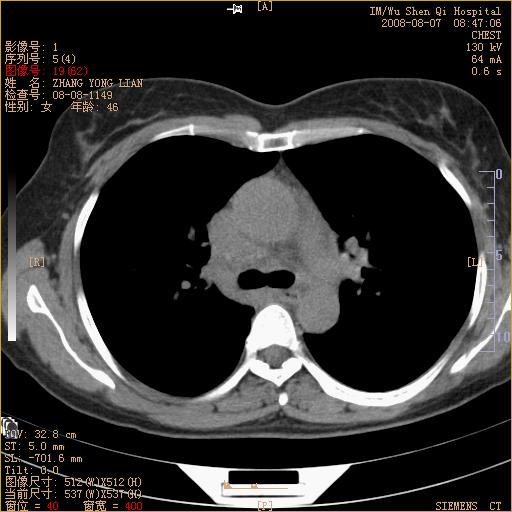

标题: CT15050:女,46岁,咳嗽胸痛一月余 [打印本页]

标题: CT15050:女,46岁,咳嗽胸痛一月余

纵隔窗没发全,左下肺近胸膜处结节。有长毛刺,纵隔淋巴结增大,不排除恶性病变。

考虑肺癌

考虑左肺下叶后基底段周围型肺癌伴纵隔淋巴结转移可能性大。

左下肺ca并纵隔及左肺门区淋巴结转移。

脾脏低密度结节转移不排除。

1)考虑左肺下叶后基底段周围型肺癌伴纵隔淋巴结转移。2)脾内低密度灶,性质待定;不排除转移瘤可能。

考虑左肺下叶后基底段周围型肺癌伴纵隔及肺门淋巴转移。